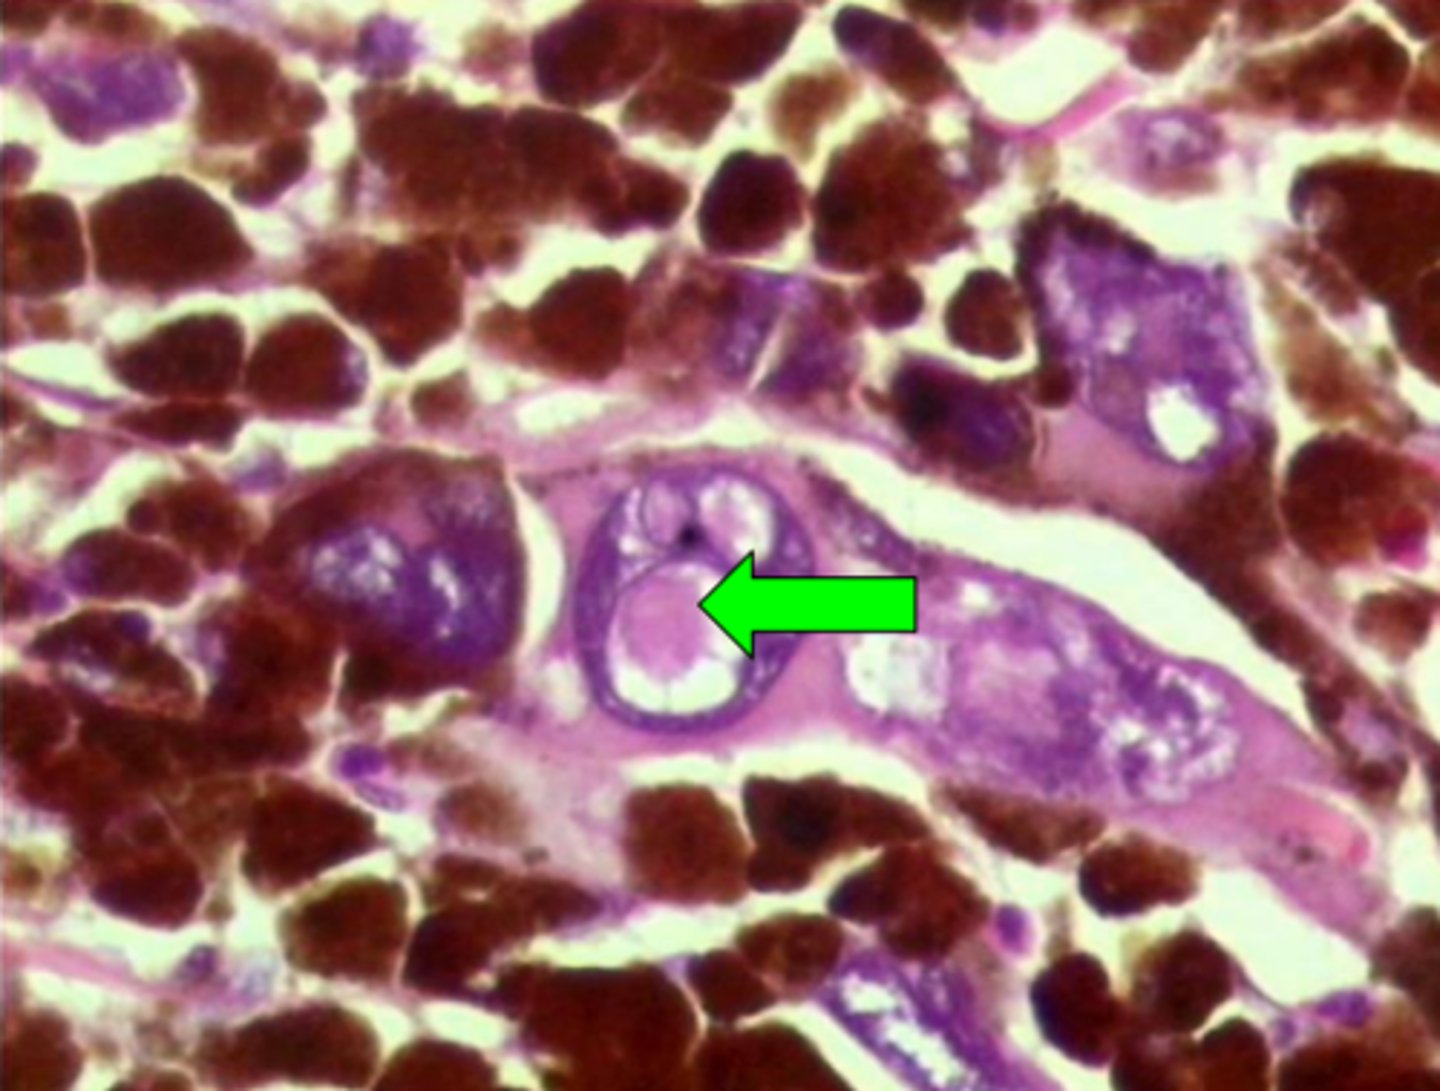

Melanoma: INCI (intranukleāri citoplazmatiski ieslēgumi)

7

New cards